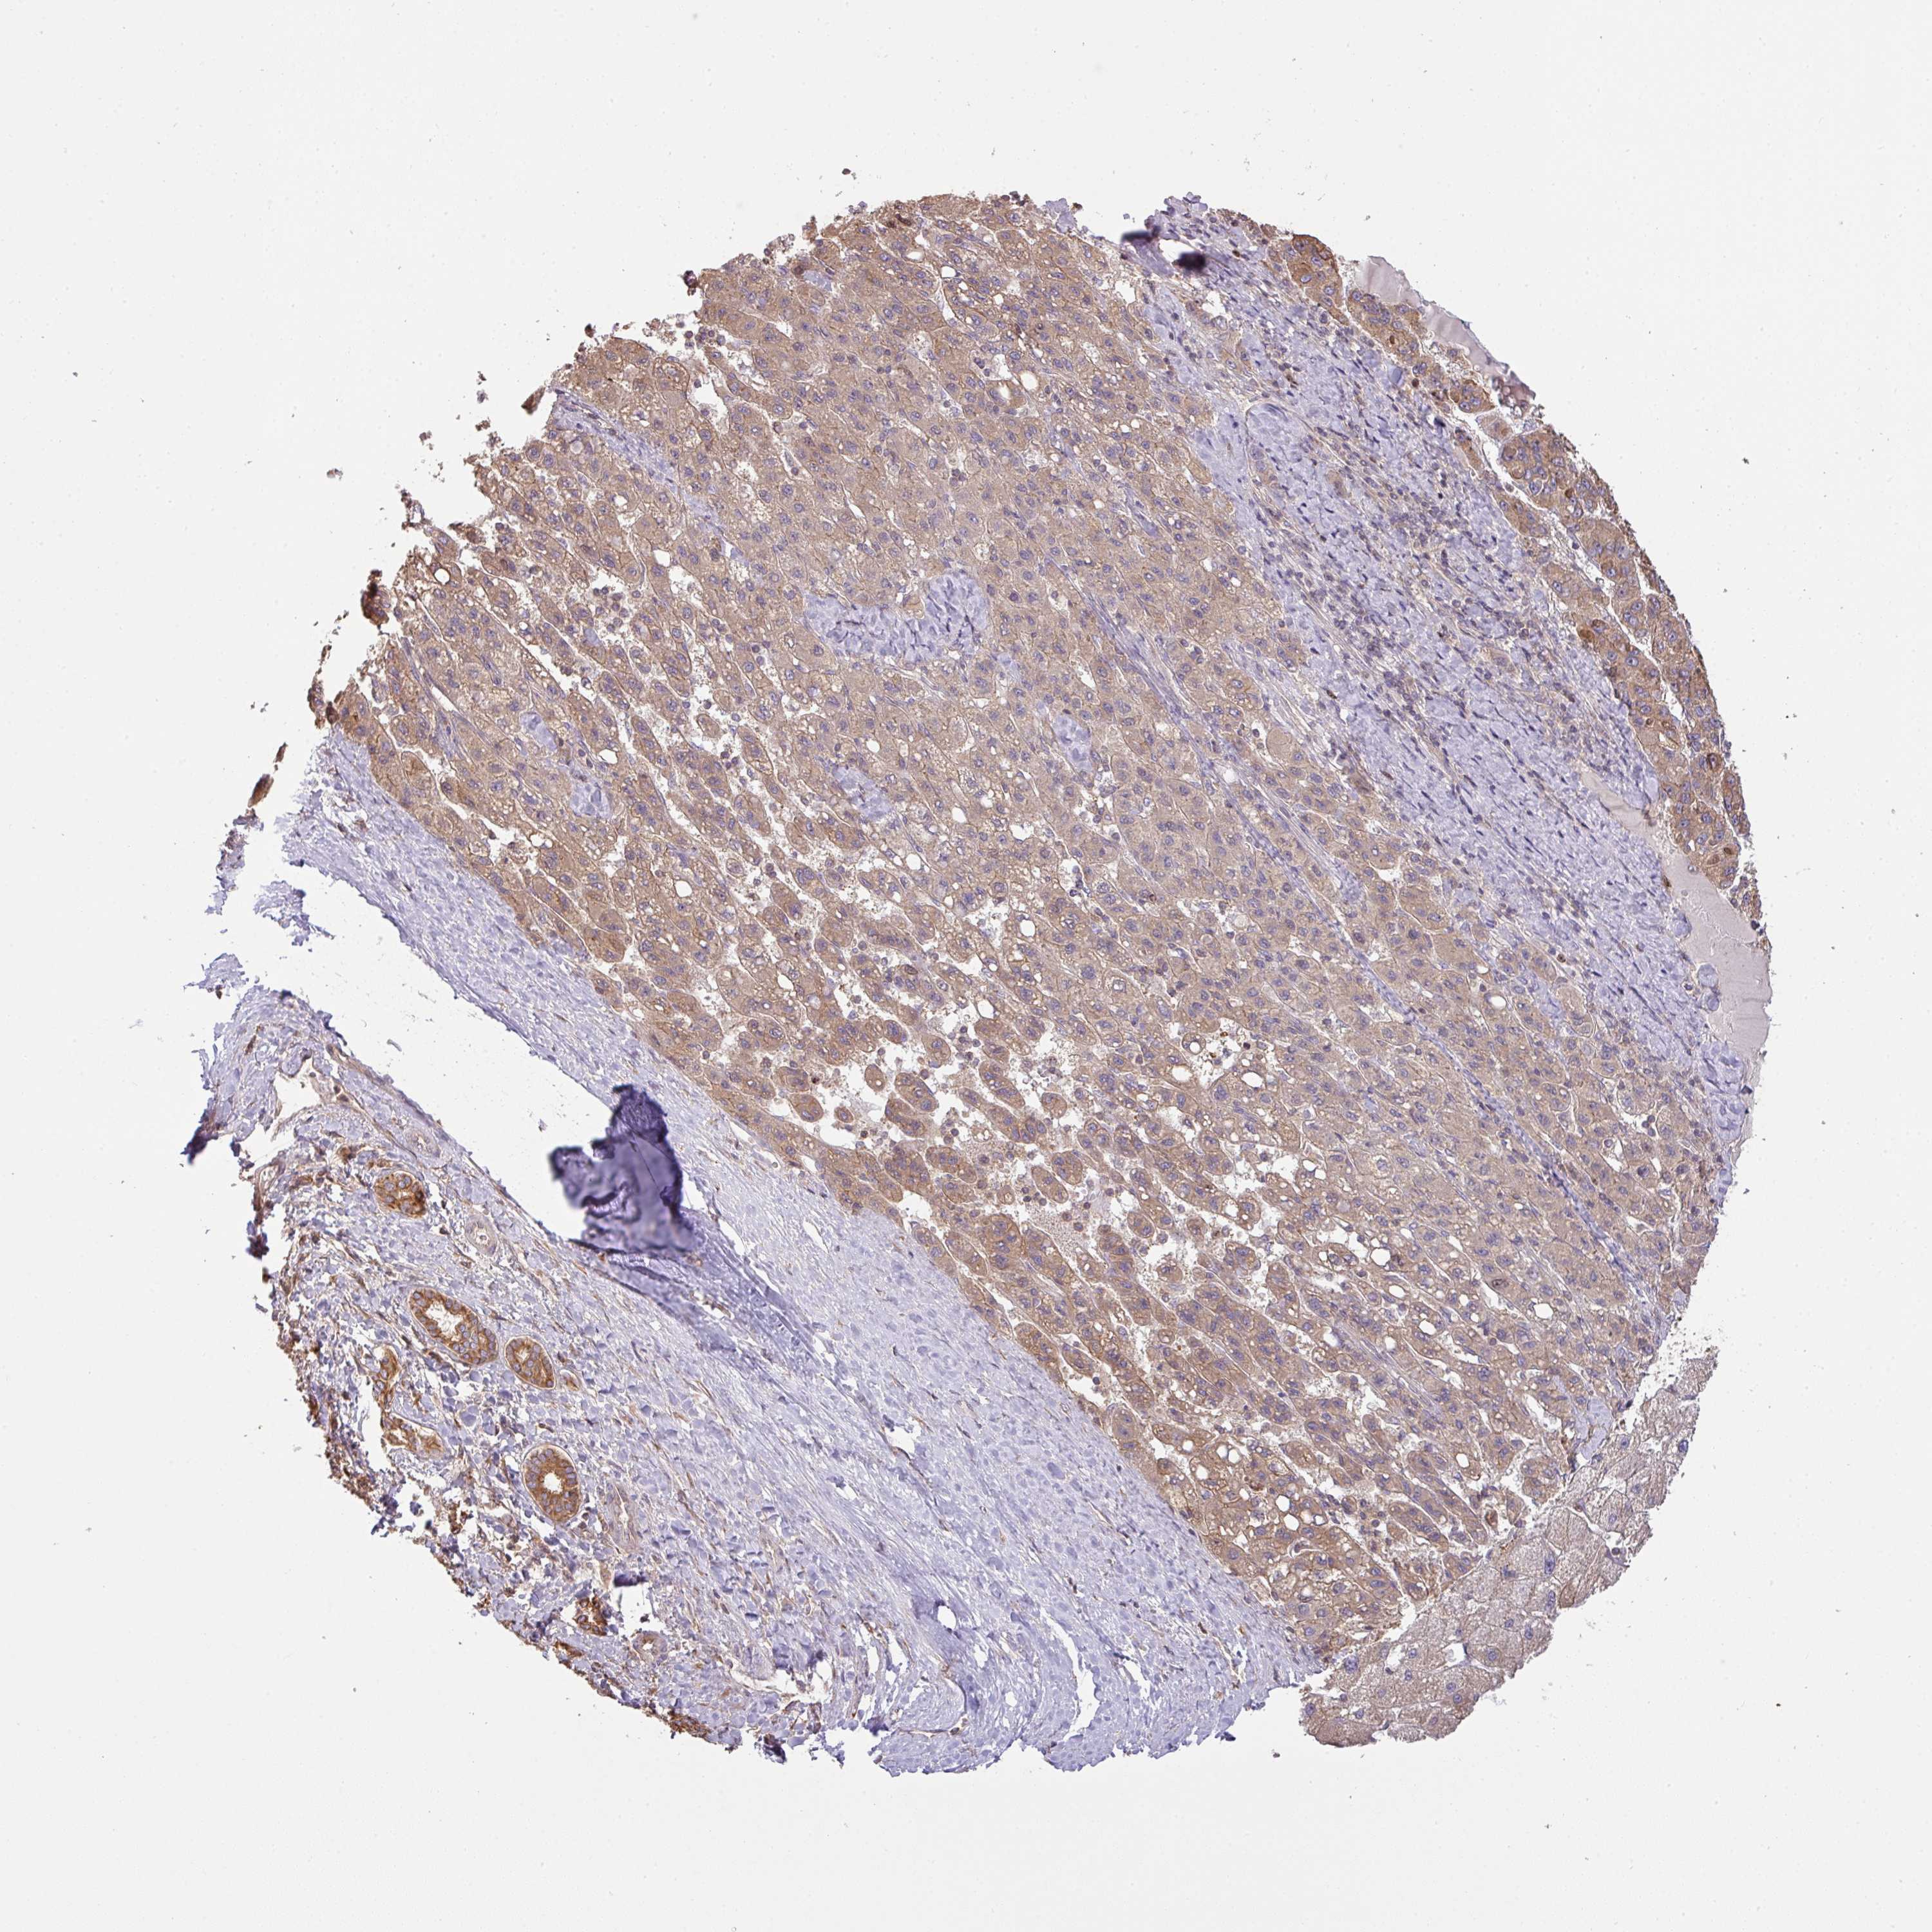

LIVER CANCER - Protein expressioni

A mouse-over function shows sample information and annotation data. Click on an image to view it in a full screen mode. Samples can be filtered based on level of antibody staining by selecting one or several of the following categories: high, medium, low and not detected. The assay and annotation is described here.

Note that samples used for immunohistochemistry by the Human Protein Atlas do not correspond to samples in the TCGA dataset.

Antibody stainingi

Antibody staining in the annotated cell types in the current human tissue is reported as not detected, low, medium, or high, based on conventional immunohistochemistry profiling in selected tissues. This score is based on the combination of the staining intensity and fraction of stained cells.

Each image is clickable and will lead to virtual microscopy that enables deeper exploration of all samples and also displays staining intensity scores, fraction scores and subcellular localization as well as patient and tissue information for each sample.

Antibody HPA050955

Staining

High

Medium

Low

Not detected

Intensity

Strong

Moderate

Weak

Negative

Quantity

>75%

75%-25%

<25%

None

Location

Nuclear

Cytoplasmic/membranous

Cytoplasmic/membranous,nuclear

Cholangiocarcinoma

Carcinoma, Hepatocellular, NOS